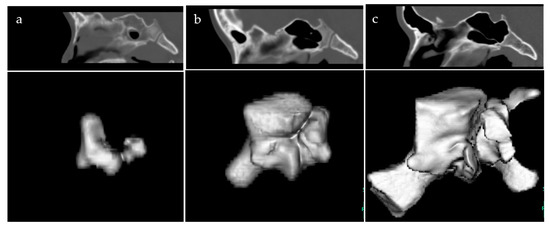

2.2. Three-Dimensional Computed Tomography